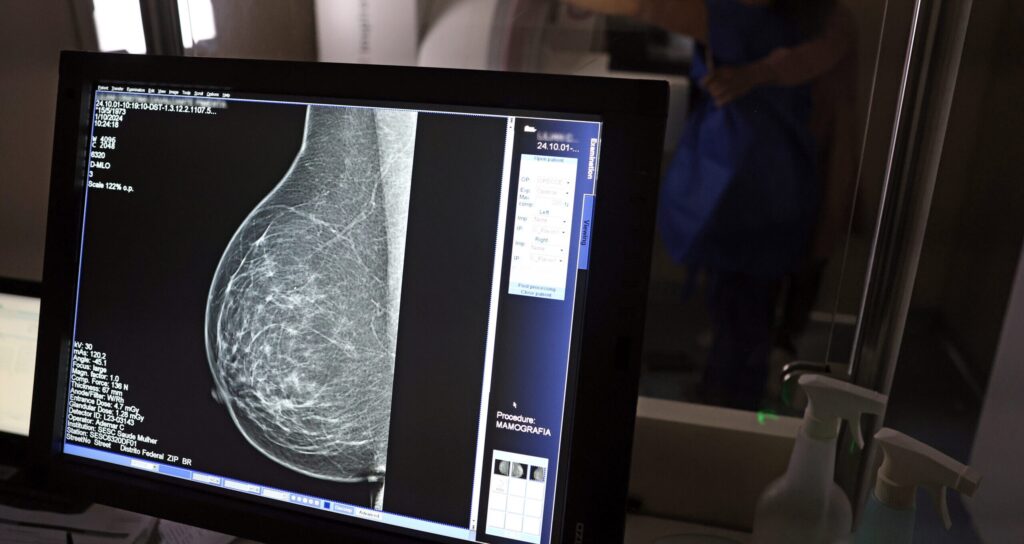

A inteligência artificial (IA) vem se mostrando uma ferramenta promissora na identificação do risco de doenças cardiovasculares em mulheres, utilizando mamografias como base para a análise. Um recente estudo da Sociedade Europeia de Cardiologia, veiculado na renomada revista ‘European Heart Journal’, destaca a capacidade da IA em detectar a presença de calcificações arteriais a partir de exames de raio-X, que, tradicionalmente, são utilizados para o rastreamento de câncer de mama.

A calcificação arterial nas mamas, que frequentemente aparece durante mamografias de rotina, não está relacionada diretamente a tumores, mas pesquisas apontam uma conexão entre a presença dessas calcificações e fatores de risco cardiovascular, além do potencial desenvolvimento de doenças cardíacas no futuro. Essa descoberta pode ter implicações significativas na detecção precoce de problemas cardíacos entre mulheres.

O estudo envolveu a participação de 123.762 mulheres que se submeteram ao rastreamento mamográfico e que não possuíam histórico de doenças cardiovasculares. A equipe de pesquisadores utilizou IA para analisar a quantidade de depósitos de cálcio nas artérias do tecido mamário, classificando essa calcificação em grande, moderada, leve ou ausente.